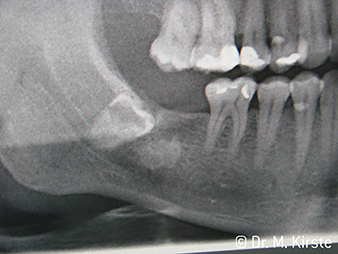

Surgical drive instruments face anatomical limits when extracting wisdom teeth: the cheek obstructs straight handpieces in the case of small mouths. Or the distal molar makes burr access difficult for contra-angle handpieces. In either case, the new surgical contra-angle handpieces from W&H offer an intelligent solution – even for wide apical tooth sectioning.

The dental handpieces WS-91 and WS-91 L G combine the advantages of surgical straight and contra-angle handpieces for the first time ever (Fig. 1). The extended angle between the shank and burr axis allows good access to the tooth row both buccally and occlusally (Fig. 4). Displaced teeth can be comfortably sectioned (Fig. 6 and 7). The dentist also has a significantly better view of the surgical site than with the instruments previously available. Dr. Mario Kirste from Frankfurt/Oder had this to say, “If I turn the contra-angle handpiece head slightly, I can work particularly quickly and safely in the retromolar region. The instrument has the potential to reconcile the contrasting positions taken up by the users of straight and contra-angle handpieces.” (Fig. 2-5)